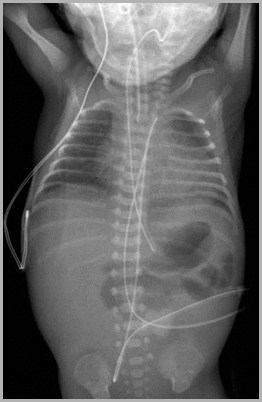

Two UACs, one at T7, the other at L3UVC in portal vein

T7

L3